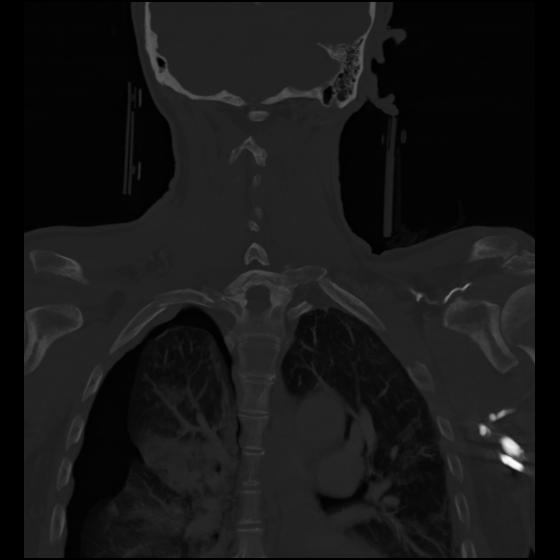

23 ANGIO,CE,Cor-MIP,5.000,ANGIO,Cor-MIP,